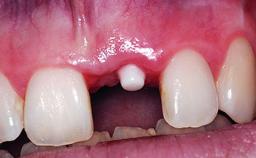

Replacement of an Upper Right Central Incisor with Root Resorption: Ridge Preservation, Delayed Placement of an NC Bone Level Roxolid Implant

A 32-year-old female Caucasian patient with a compromised maxillary right central incisor was referred to us by a general dentist. Her chief complaints were discomfort and mobility of tooth 11 with unsatisfactory esthetics due to discoloration. The patient reported a previous trauma, some years earlier, as the origin of pathology on the afflicted tooth. Anamnesis was negative for any other dental or periodontal pathology in the remaining dentition. The patient did not take any medication and reported to be a light smoker (5–10 cigs/day). She had high esthetic expectations of her treatment. The extraoral examination revealed a high smile line with full exposure of her maxillary teeth and surrounding soft tissue in the area between the second premolars.

Type of Implants Reduced-Diameter|Two-Piece